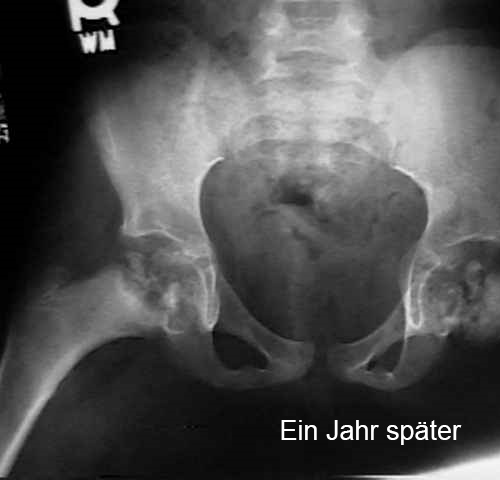

Der Hüftkopf stirbt teilweise oder vollständig ab. Der Körper löst dies, indem er neues Knochengewebe bildet und den abgestorbenen Knochen abbaut. Das neue Knochengewebe ist noch sehr schwach, wodurch die Hüfte weniger rund wird oder es sogar zu einer Absenkung kommt. Dies führt zu einer Verformung des Hüftgelenks. Die Abbildungen zeigen die Entwicklung der Hüfte eines Kindes mit Morbus Calvé-Legg-Perthes.